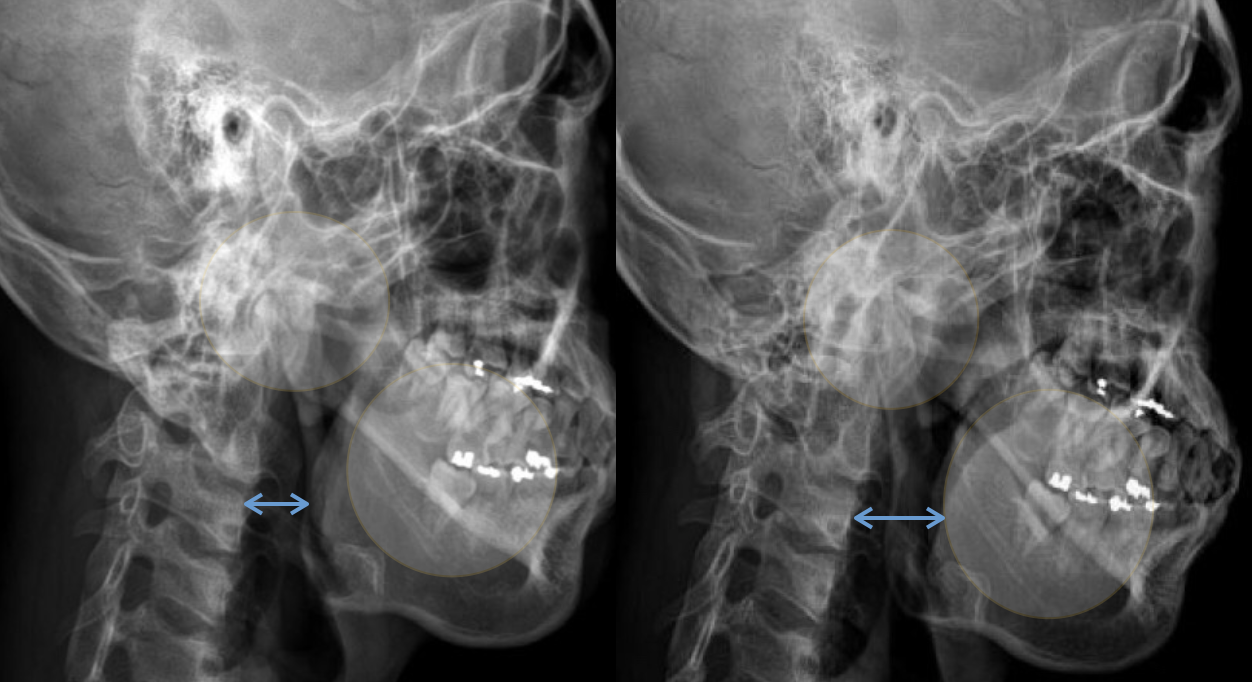

아래턱이 교합 문제나 경추의 아탈구로 뒤로 밀리게 되면 비강에서 이어지는 airway는 좁아지게 됩니다. 아래 엑스레이 사진을 보면 왼쪽 영상의 경우 정상에 가까운 airway 상태이며 오른쪽은 하악이 후방 이동하면서 airway가 좁아져 있는 것을 보여주고 있습니다. 실제로 오른쪽 환자의 경우 심한 비염 증상과 함께 코골이와 수면 무호흡증으로 양압기를 사용하고 있었으며 만성적인 뒷목, 어깨 통증과 함께 얼굴비대칭과 턱관절 장애가 동시에 진행되어 있습니다.

아래턱의 위치에 따른 airway의 변화 ( 왼쪽 : 정상 / 오른쪽 : 좁아진 airway)

이 엑스레이 영상에서는 뒤로 밀려있던 턱이 앞으로 이동하면서 airway의 직경이 개선되는 것을 확인해볼 수 있습니다.